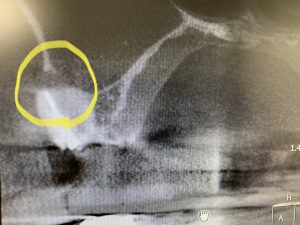

本日の根管治療で珍しい根管形態の側枝が観られました

(右上5番の症例)

根管の尖端付近が枝分れしています

このようにな『側枝』が空洞化していると、根管の感染が再燃する一因になります。

C Tでも分かりますね